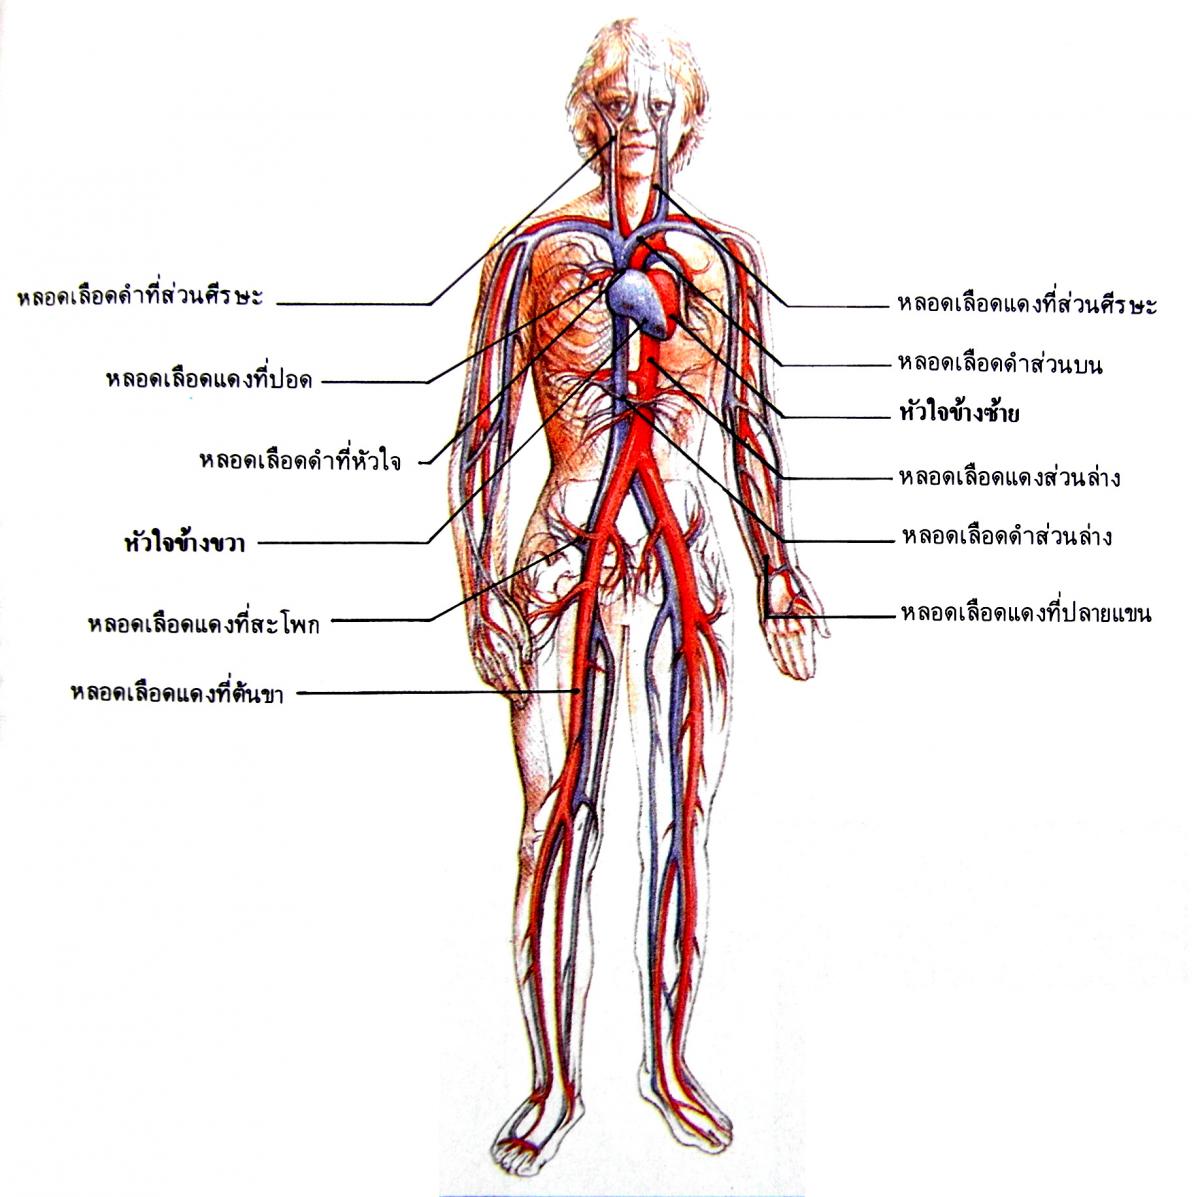

ปอด ภาพประกอบสต็อก – ดาวน์โหลดรูปภาพตอนนี้ – iStock กายวิภาคของระบบไหลเวียนโลหิต ภาพประกอบสต็อก – ดาวน์โหลดรูปภาพตอนนี้ …

กายวิภาคของระบบไหลเวียนโลหิต ภาพประกอบสต็อก – ดาวน์โหลดรูปภาพตอนนี้ … ดาวน์โหลดฟรี | ระบบไหลเวียนเลือดการออกแบบ, แขน, ศิลปะ png | PNGEgg

อวัยวะภายในของมนุษย์ของหัวใจที่มีระบบไหลเวียนโลหิตกายวิภาค Xray 3d … หลอดเลือดแดงและระบบไหลเวียนโลหิตของมนุษย์และกายวิภาคของหลอดเลือดดํา ภาพ …

หลอดเลือดแดงและระบบไหลเวียนโลหิตของมนุษย์และกายวิภาคของหลอดเลือดดํา ภาพ … ระบบไหลเวียนโลหิต #EP-515

หลอดเลือดในร่างกายมี 3 ชนิด แสดงแบบจำลองกายวิภาคศาสตร์การไหลเวียนโลหิตรวมถึงระบบหัวใจและหลอดเลือด …